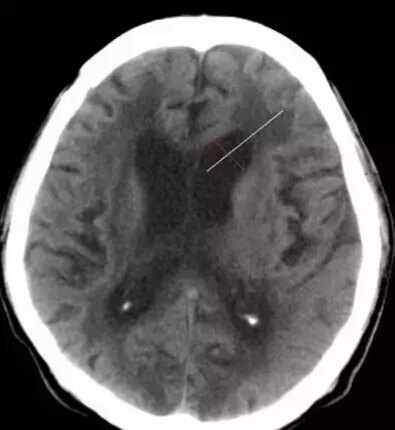

第二招:额角比率-垂直于额角长轴测量额角的最宽部分 脑萎缩-小

脑积水~宽